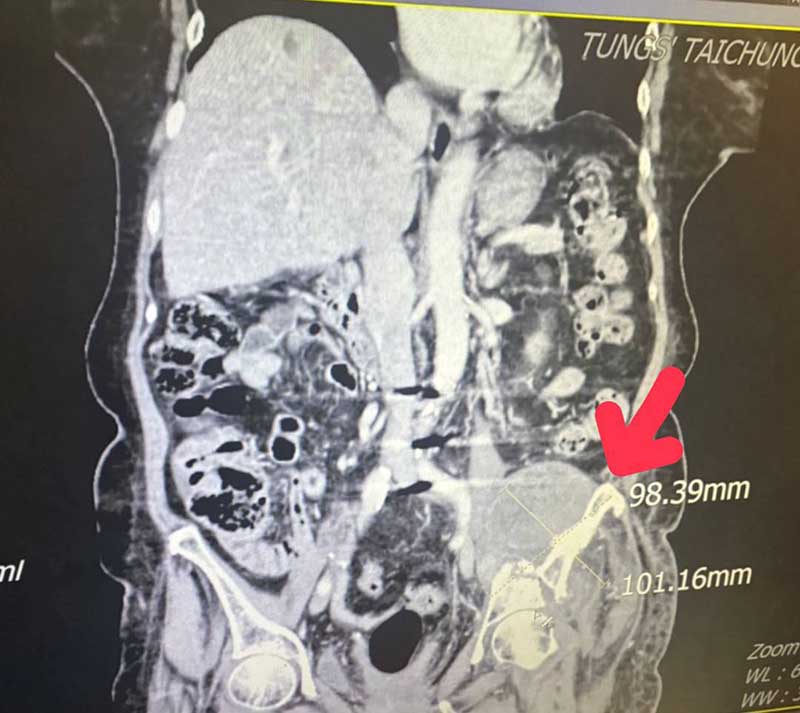

因腫瘤細胞太大(12.1公分x17.4公分左右),並且腫瘤位置執行手術風險過高,轉由放射腫瘤科葉啟源主任進行銳視刀適應性放射治療,利用空間分割點狀治療方式(Spatially Fractionated Radiation Therapy, SFRT) 在局部的位置給予點狀高劑量的放射線,再配合傳統銳視刀治療方式,經過一個月26次治療後,腫瘤已經縮小至9.8公分x10.1公分左右,縮小腫瘤後也讓疼痛獲得明顯改善。

紅色箭頭即為進行銳視刀適應性放射治療利用空間分割點狀治療方式,配合傳統銳視刀治療方式,治療後腫瘤已經縮小至9.8公分x10.1公分左右